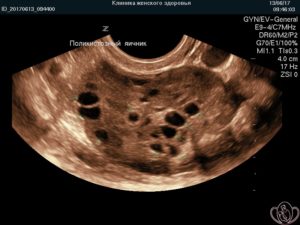

- Характерная УЗ – картина яичников: наличие более 12 фолликулов в каждом яичнике и/или увеличение объема яичников более 10 мл. Из-за такой особенности их еще называют мультифолликулярные яичники.

При СПКЯ яичники имеют характерную ультразвуковую картину. В них имеется множество мелких фолликулов по периферии яичника, их иногда называют «ожерельем». Обычно это 9-12 фолликулов диаметром до 9 мм. За счет разрастания стромы яичника (ткань которая окружает фолликулы) увеличивается и объем яичников, обычно он более 10 мл.

При прогрессировании мультифолликулярных маточных придатков на ультразвуковом исследовании доктор выявляет большое количество созревших фолликулов (более двенадцати штук), которые готовы к овуляционному периоду.

Отличие МФЯ от ПКЯ выявляется на подробном обследовании. При поликистозе отмечаются такие изменения:

- Диаметр яичников увеличивается до девяти сантиметров;

- Утолщению подвергаются внутренние капсулы парного органа;

- Значительно увеличиваются фолликулы;

- Отсутствие овуляционного периода;

- Гормональный дисбаланс.

Мультифолликуряным изменения присущи:

- Увеличение яичников до шести сантиметров;

- Толщина стенок органа не утолщается;

- Размер фолликулярных капсул не превышает восемь миллиметров;

- Овуляционный период наступает своевременно;

- Уровень гормонов остается стабильным.